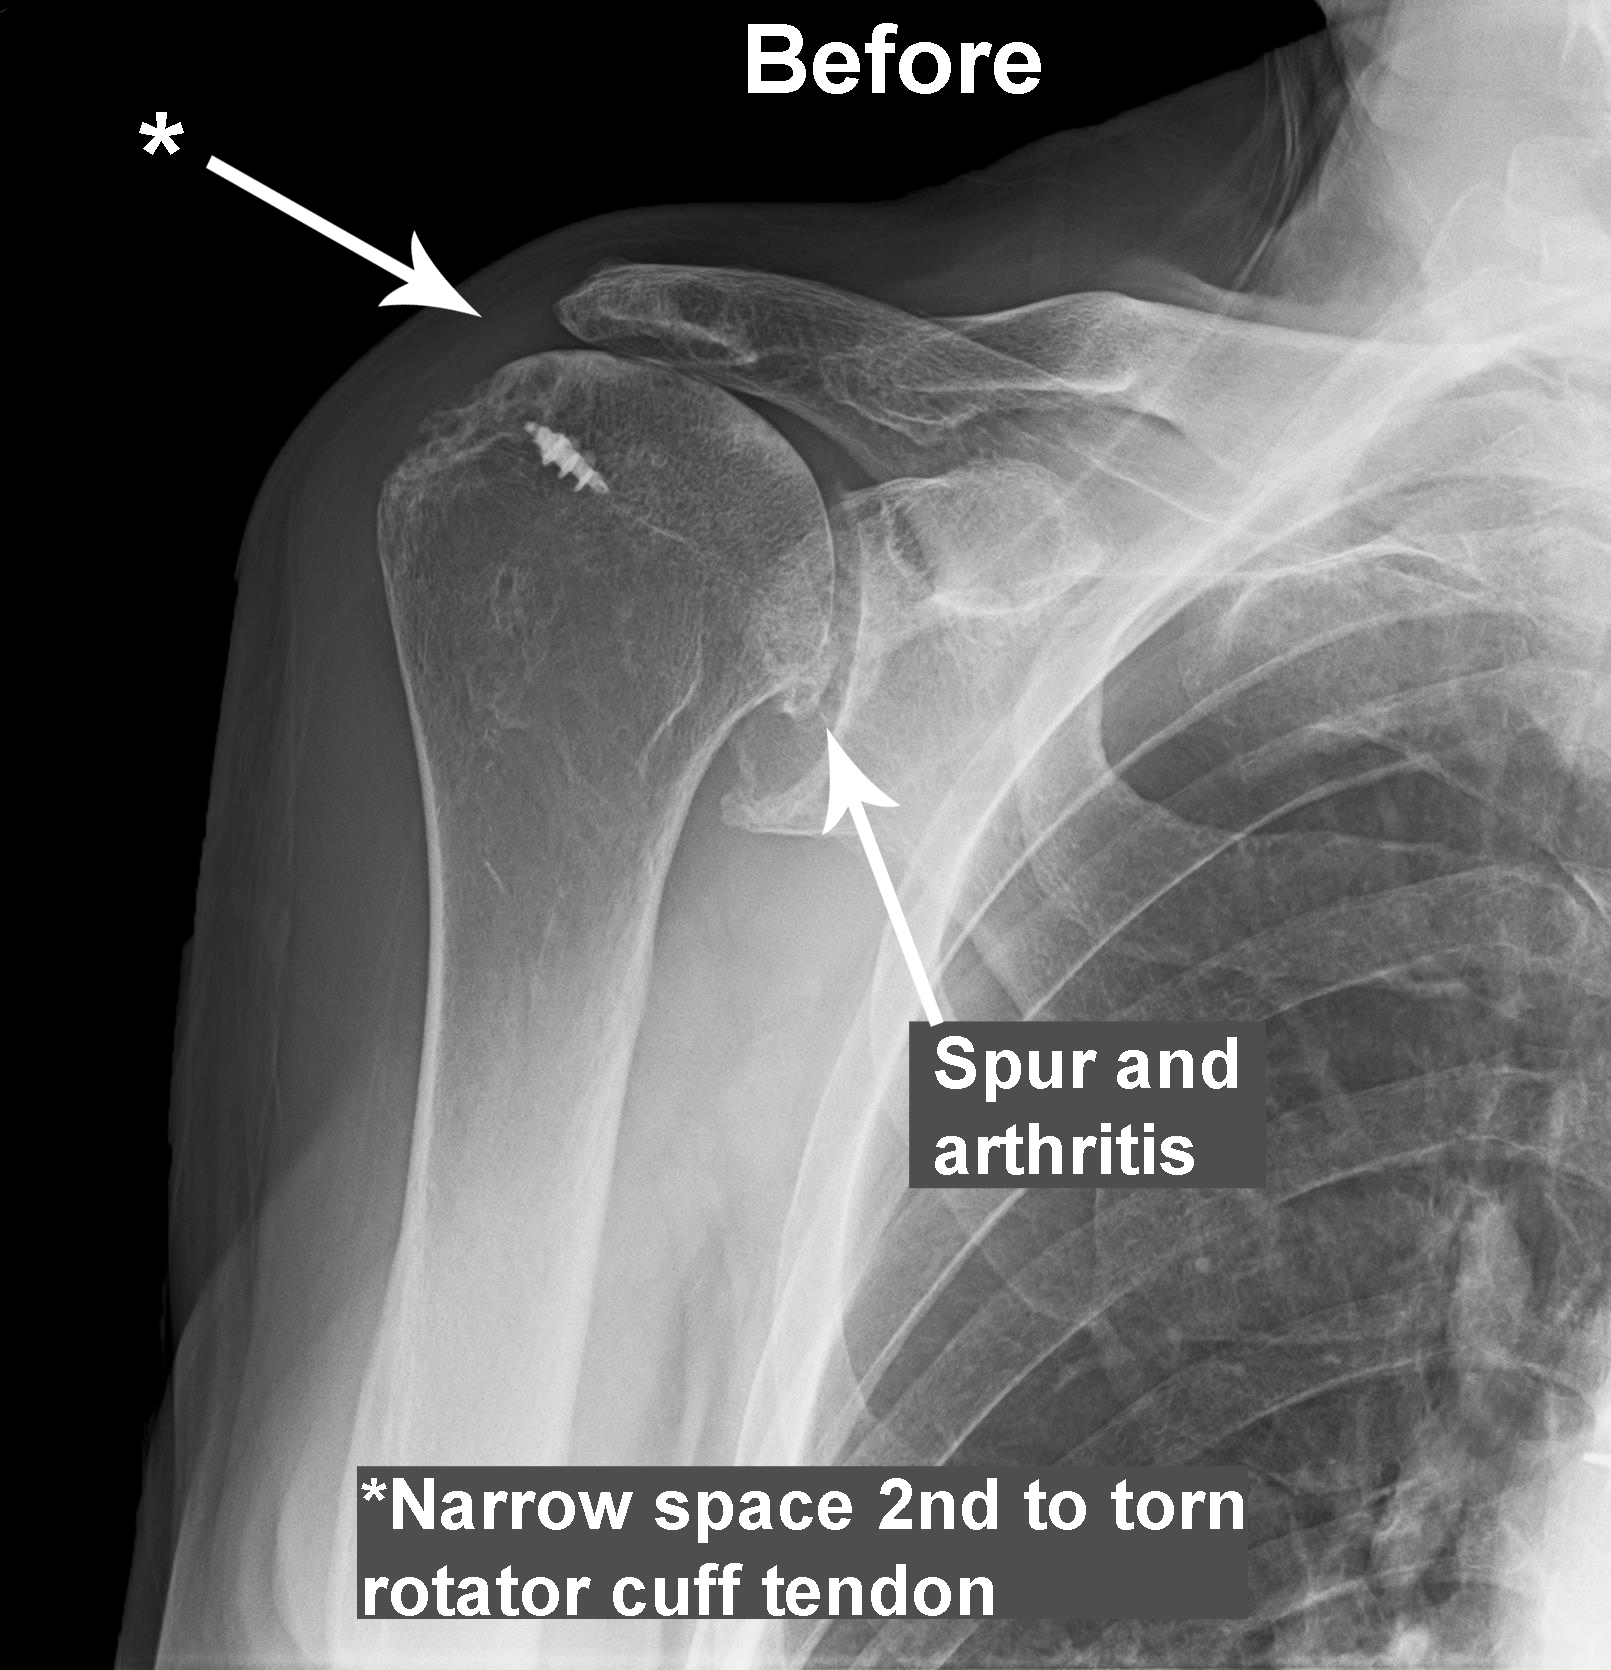

Shoulder Arthritis / Rotator Cuff Tears: causes of shoulder pain: B2 …

Shoulder Arthritis / Rotator Cuff Tears: causes of shoulder pain: How …

Shoulder Arthritis / Rotator Cuff Tears: causes of shoulder pain …

Shoulder Arthritis / Rotator Cuff Tears: causes of shoulder pain …

Shoulder Arthritis / Rotator Cuff Tears: causes of shoulder pain …

Shoulder Arthritis / Rotator Cuff Tears: causes of shoulder pain …

Shoulder Arthritis / Rotator Cuff Tears: causes of shoulder pain …